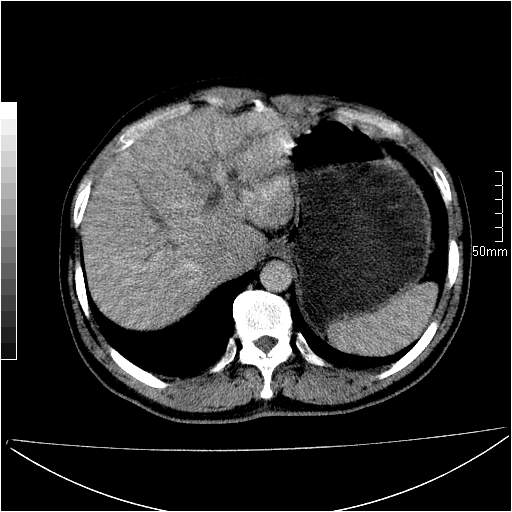

男性,54岁,皮肤黄染,搔痒一周余.b超示肝左叶回声异常.初步诊断1胆总管下段结石2胆囊结石伴慢性胆囊炎请各位战友帮忙看一下肝脏多发低密度如何解释恰当.增强效果不是很好.请大家见谅.

首先,胆总管下端结石梗阻伴肝内胆管扩张可确定。

既然做了增强,为什么光提供延时期片子,肝动静脉期肝右叶前下段病灶增强如何?另外胆囊壁增厚,欠规整,内密度不均,与肝右叶病灶分界不清,增强表现怎样?肝内胆管轻度扩张,胆总管扩张,但未见明显结石影,也应提供增强早期图像才好鉴别扩张原因。片子较清,但不够完整,暂考虑1.胆囊癌肝局部浸润,或肝癌胆囊侵犯,2.胆总管下端或胰头钩突部占位。总之本人看不明白,请高手画图指示,先谢了!

由于胆囊窝内结构显示不清,肝脏病灶又邻近胆囊窝首先考虑胆囊癌肝受侵犯。而后因肝脏病灶强化有渐进改变,且相邻胆管扩张,故考虑肝胆管细胞癌待排。

左肝胆管细胞癌。

胆总管下端结石。